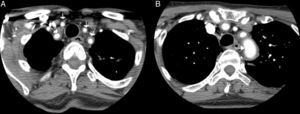

Case ReportOur patient was a 65-year-old woman with a history of bronchial asthma, with bronchiectasis, and PsA with mixed erosive involvement; she was negative for HLA-B27. She had received methotrexate and leflunomide from 2011 until 2013, when they were interrupted because of remission. She was presented with a 2-month history of fever and weakness, but did not report headaches, vision disorders or chest, abdominal or limb pain. Physical examination revealed only a difference in arterial blood pressure of 20mmHg and that some pulse rates were lower in left limbs. The temporal arteries were not tender on palpation, and the pulse rate was normal and symmetric. Laboratory tests showed a hemoglobin concentration of 9.9g/dL (normal: 12.0–15.0), erythrocyte sedimentation rate of 102mm/h (0–20), C-reactive protein 140.90mg/L (<5mg/L) and iron 11μg/dL (35.0–145.0). The remaining parameters were normal (thyroid-stimulating hormone, creatine phosphokinase, Mantoux test, tumor markers, protein profile, serological tests, immunological tests, urinary sediment and cultures). Chest radiography, echocardiogram, gastroscopy with duodenal biopsy and colonoscopy were normal. Chest and abdominal computed tomography (CT) showed stable bronchiectasis and thickening of the abdominal aortic wall, indicative of aortitis. Computed tomography angiography (CTA) (Fig. 1) also showed evidence of concentric inflammatory thickening of the supra-aortic trunks and aortic arch. Temporal artery biopsy was performed with the histological confirmation of GCA. Treatment was begun with corticoids at a tapering dose starting with 2mg/kg/day and methotrexate at 15mg/weekly, and the symptoms disappeared.

Computed tomography angiography: the presence of a concentric inflammatory thickening/vasculitis of all the supra-aortic branches (A) and of the aortic arch (B) is confirmed (arrows). The greatest involvement appears to be that observed in left subclavian artery, and there is no evidence of significant stenosis at any point. In the carotid territory, only the common carotid artery is affected, there being no extension to internal carotid artery.